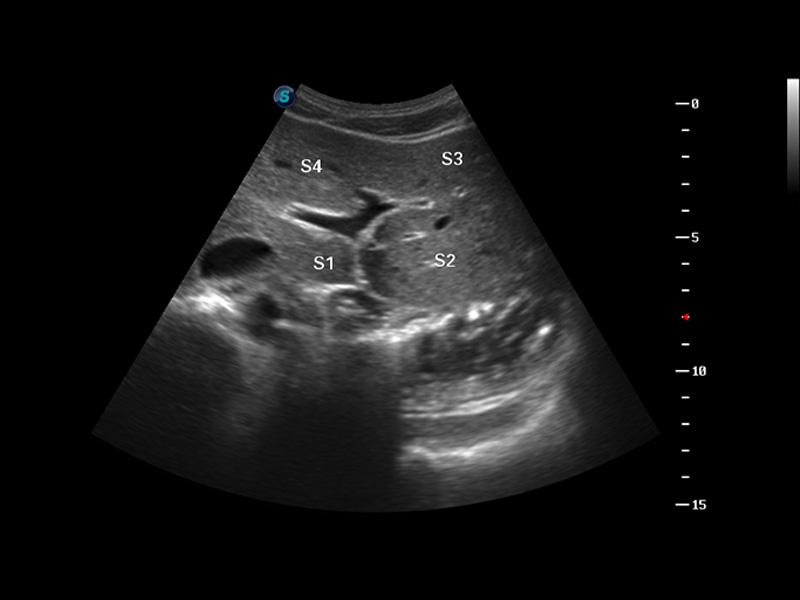

S8 EXP便携式彩色多普勒超声诊断仪是诸侯快讯官网研发的高端全身应用型便携彩超。高通道的VIS平台融合可视化(Visual)、智能化(Intelligent)和人性化(Smart)的特点,配以诸侯快讯官网自主研发生产的探头大家族,使您能够快速、准确的获得病人信息,提高工作效率的同时减轻疲劳。

μ-Scan微米成像